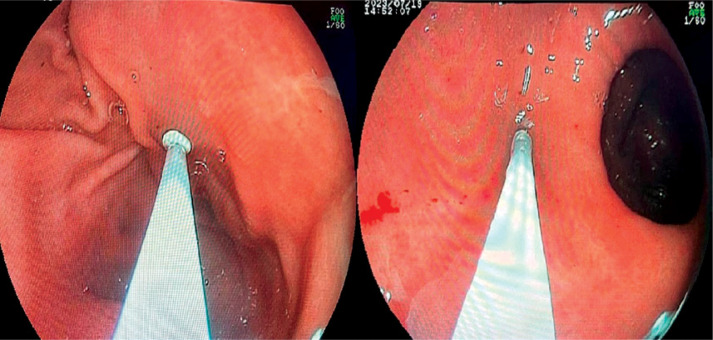

Material and methods: From 2021 to 2023, we conducted a retrospective analysis of patients who underwent intragastric BT-A injections in a general surgery endoscopy unit. The inclusion criteria were being aged 18-65 and having a body mass index (BMI) over 25 kg/m2. Patients with specific medical conditions or incomplete records were excluded. We monitored patient weight and BMI values before the procedure and at monthly intervals, with further assessments conducted in the sixth month, including appetite and patient satisfaction.

Results: Our study on 67 patients, predominantly female (82.1%), aged 35.5 ±9.0 years with a mean BMI of 33.5 ±3.3 kg/m², examined BT-A injections' effectiveness. 58.2% received injections in both gastric antrum and fundus regions, showing greater weight loss (mean: 10.7 ±7.0 kg) than those treated in the antrum alone. Side effects occurred in 16.4%, with various symptoms. High dietary compliance (80.6%) correlated with weight loss, especially among those reporting intense satiety. Patient satisfaction positively correlated with weight loss, highlighting treatment efficacy and patient response to dual-region injections.